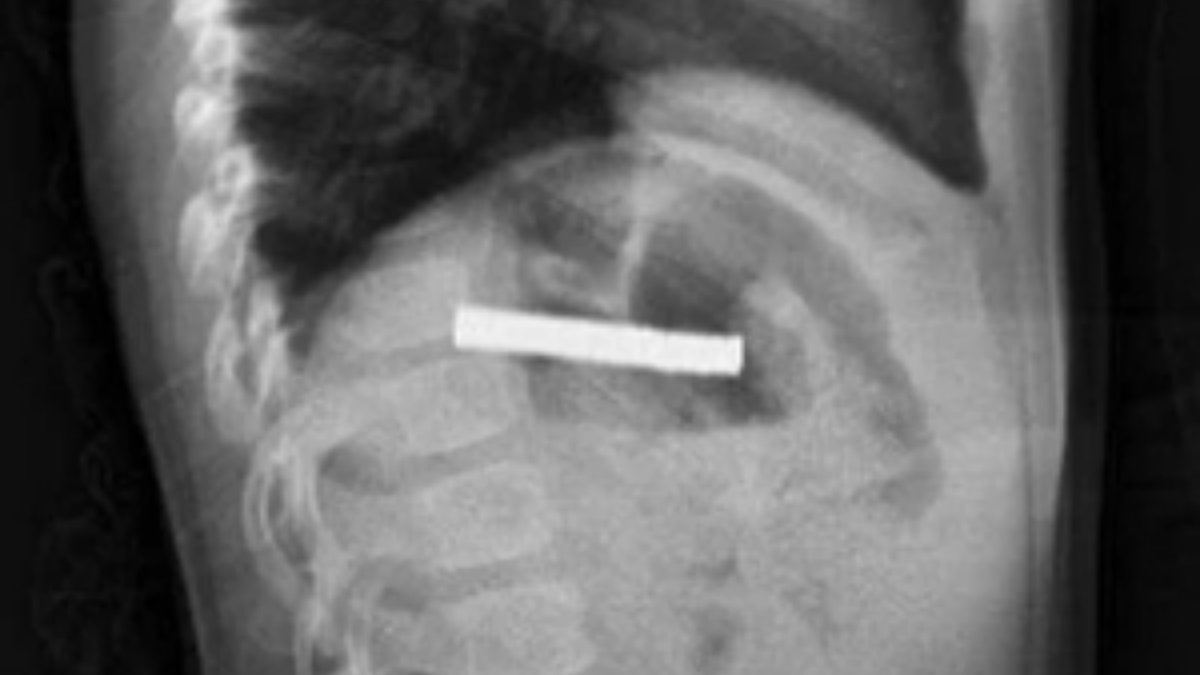

Erzurum’da 3 yaşındaki bir çocuk evde bulunan 19 mıknatısı yuttu. Elazığ’daki Fırat Üniversitesi Hastanesi’nde Prof. Dr. Yaşar Doğan tarafından yapılan endoskopik operasyonla mıknatıslar çıkarıldı. Yemek borusu ve mide girişinde zedelenmeler oluşsa da küçük çocuğun sağlık durumunun iyi olduğu ve taburcu edildiği bildirildi.

Fırat Üniversitesi Çocuk Gastroenteroloji Hepatoloji ve Beslenme Bilim Dalı Başkanı Prof. Dr. Yaşar Doğan, çocuk hastanın yemek borusuna yapışmış 19 mıknatısı endoskopik yöntemle çıkardı.

Mıknatıslar uzun süre yemek borusunda takılı kaldığı için yemek borusu ve mide girişinde zedelenmeler olurken, çocuğun sağlık durumunun iyi olduğu ve taburcu edildiği öğrenildi.